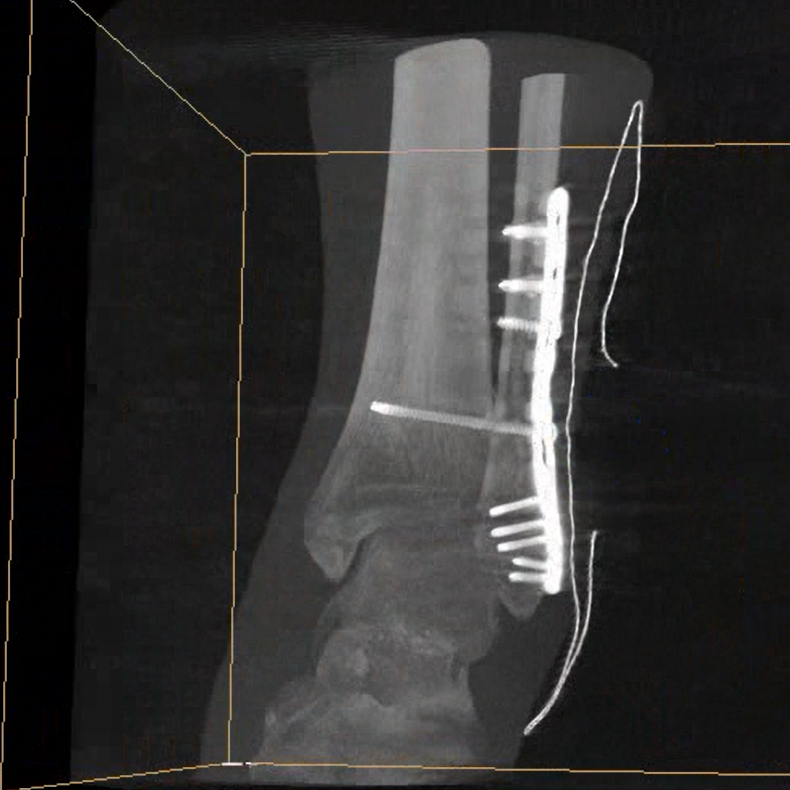

術(shù)中三維成像和橫斷面圖像提供多角度的手術(shù)診斷信息,輔助醫(yī)生進行術(shù)中評估判斷,諸如骨折復位情況和內(nèi)植入螺釘?shù)某叽绾臀恢茫o助手術(shù)更好地完成。

在C臂掃描過程中,始終保持拍攝主體處于射線束的中心,避免了序列圖像采集過程中的橫縱方向運動,減少相對運動造成的運動偽影。